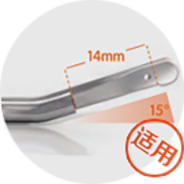

Break away from traditional treatment根据患者腋下的弧度选择适合患者最佳角度的手柄刀头量身定制祛臭专属方案。

大汗腺数量相对 较少、深度较浅 的轻微腋臭、青 春期腋臭、儿童 腋臭等